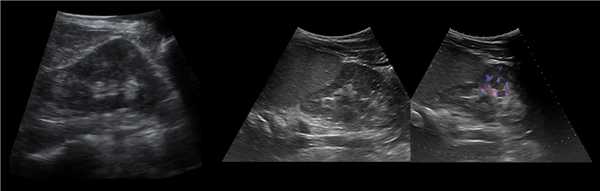

Рисунок. У новорожденного на УЗИ почек определяется гидронефроз (1) и расширенный мочеточник (2) справа. В мочевом пузыре двустороннее уретероцеле (3). При исследовании левой почки структурных изменений не выявлено.

Рисунок. На УЗИ определяется удвоенная чашечно-лоханочная система, расширена лоханка верхнего сегмента (1) и мочеточник на всем протяжение (2, 3), в мочевом пузыре уретроцеле (4). Полное или неполное удвоение чашечно-лоханочной системы возможно увидеть с помощью КТ-урографии.

Рисунок. Дистальный отдел мочеточника расширен, в мочевом пузыре анэхогенное образование с тонким и ровным контуром — уретероцеле.

Рисунок. Двустороннее уретероцеле на УЗИ: в режиме ЦДК из верхушек уретероцеле определяется выброс мочи.